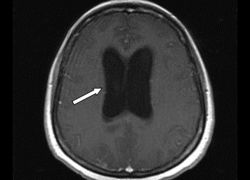

Диагностирование заболевания

Определить наличие синдрома крайне сложно, а установить диагноз с абсолютной уверенностью практически невозможно. Врожденный синдром определяется корректностью функционирования рефлексов и размерами окружности головы. Для подтверждения или выявления его у детей и взрослых проводятся обследования глазных сосудов, томографические исследования, ультразвуковая диагностика, а также пункция спинномозговой жидкости.